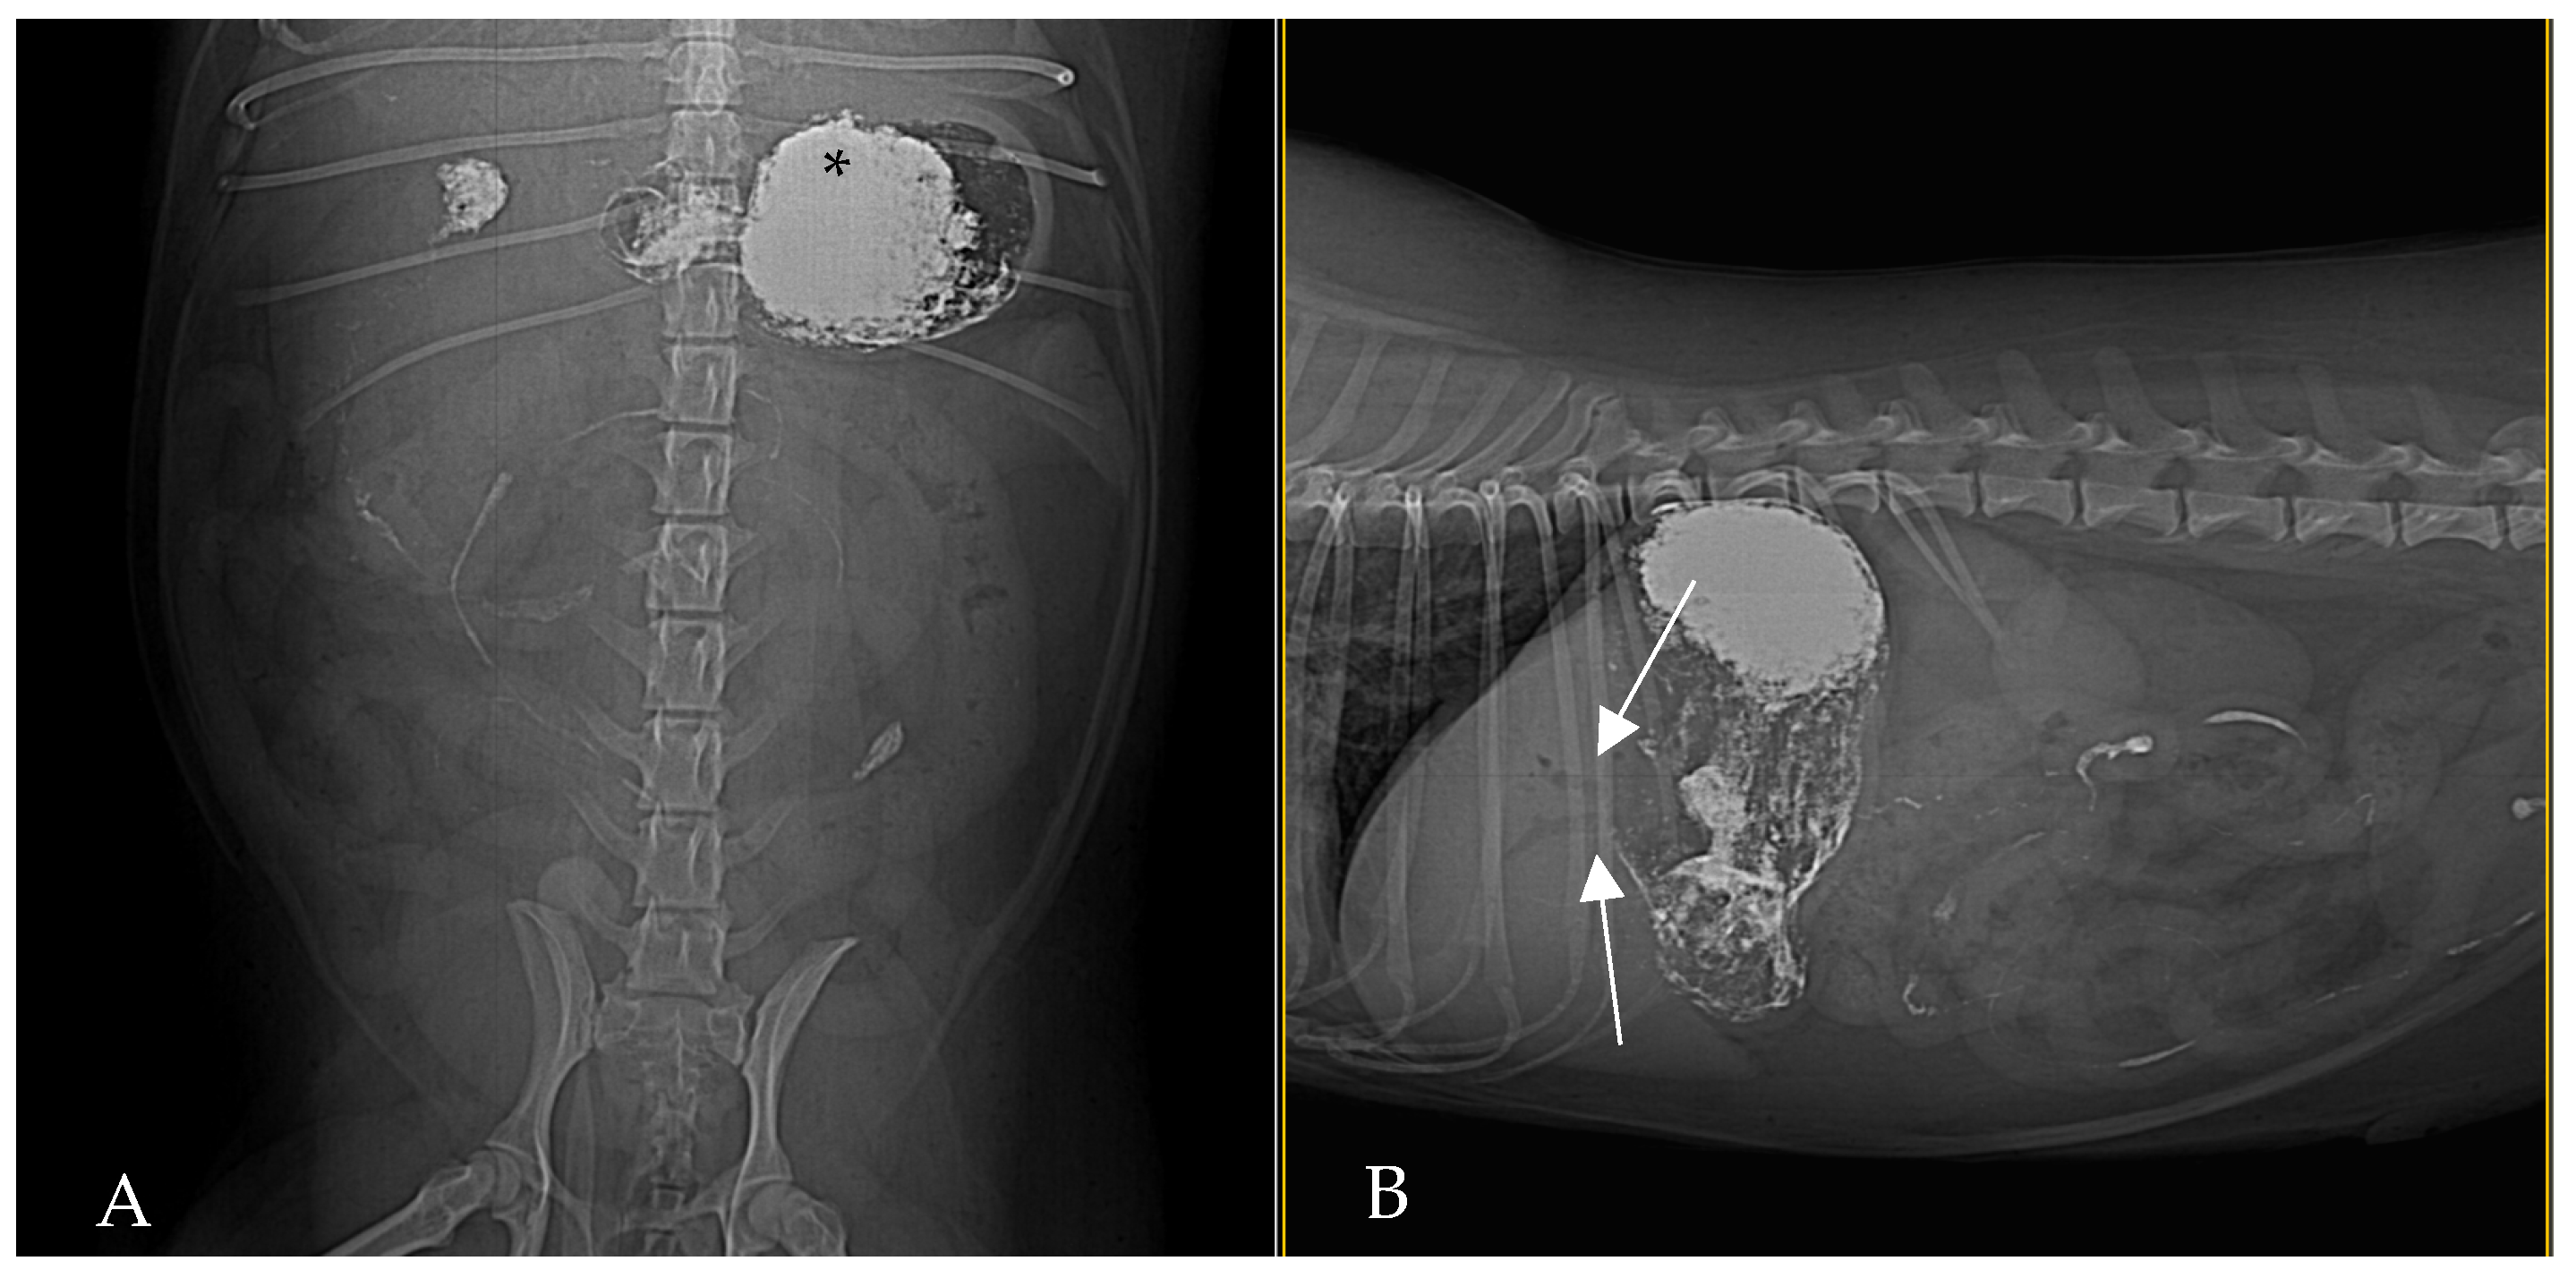

By 2 h post-barium (Figure 3) administration, radiography demonstrated biliary tree and gallbladder had become opacified with barium, indicating retrograde flow of contrast from the duodenum into the biliary ducts. This reflux was even more conspicuous in subsequent images: at 24 h post-contrast, the branching biliary tree was fully outlined by hyperattenuating contrast medium, and the gallbladder lumen was coated with barium. Concurrently, by 24 h a substantial amount of barium had reached the transverse and descending colon, increasing the opacity of the colonic contents. Barium residues cleared gradually over the next 72 h, with most of the contrast eliminated by day 3 (Figure 4).

Contrast-enhanced CT of the abdomen performed 48 h into the investigation, confirmed the presence of high-density material (barium sulfate) within the intrahepatic and extrahepatic biliary ducts. The CT also provided detailed information about the pancreas: the pancreatic parenchyma was irregularly enlarged and heterogenous, with regions of mottled hypoattenuation. Mild peripancreatic fat stranding (inflammation of surrounding fat) was evident, and multiple ill-defined, round hypoattenuating areas were present within the pancreas, consistent with abscesses or pockets of necrosis (Figure 5 and Figure 6). The common bile duct was markedly distended and filled with hyperattenuating contrast material (barium), confirming duodenobiliary reflux in cross-sectional detail (Figure 7).

Figure 3. Right lateral (A) and ventrodorsal (B) abdominal radiography at 2 h post-barium. Barium is visible outlining the biliary tree (white arrows) and is beginning to fill the gallbladder (white arrowhead). Residual contrast is also present in the stomach and intestines, and fecal matter mixed with barium is seen in the colon.